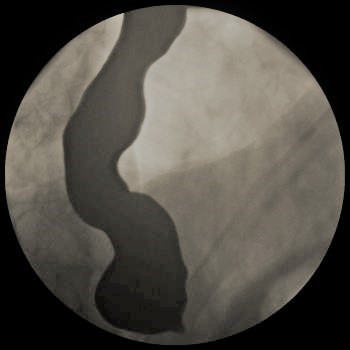

A 72-year-old gentleman with achalasia who weighed 91 kg was admitted for an elective POEM procedure (Figure 1). The procedure started with stable hemodynamics on a constant ventilator setting of respiratory rate of 10-16/hr; tidal volume of 443; positive end-expiratory pressure (PEEP) of 5 cm H2O; positive inspiratory pressure of 22-24; end tidal carbon dioxide of 28; arterial oxygen saturation of 100. However, 45 minutes into the procedure, the patient went into pulseless electrical arrest. The scope was withdrawn, and he was revived after 10 minutes of cardiopulmonary resuscitation. The procedure was aborted and he was transferred to the ICU intubated, critically ill, and on escalating doses of epinephrine and norepinephrine. Follow-up diagnostic imaging (Figures 2 and 3) showed a small heart with air tracking around it, the mediastinum, the esophagus, and the aorta, confirming tension pneumomediastinum.